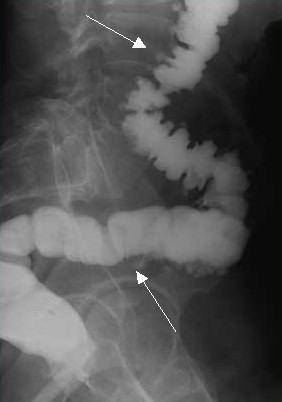

- Soit lors de la réalisation d'un lavement baryté : Ce dernier examen peut être demandé lorsqu'il existe une contre-indication à la réalisation d'une coloscopie. Le diverticule est mis en évidence devant la présence de produits de contraste à l'extérieure de la paroie colique sous la forme de "champignon".

Figure 8 : Diverticules visualisés sur un lavement baryté

Figure 9 : Diverticules multiples le long du colon visualisés

sur un lavement baryté